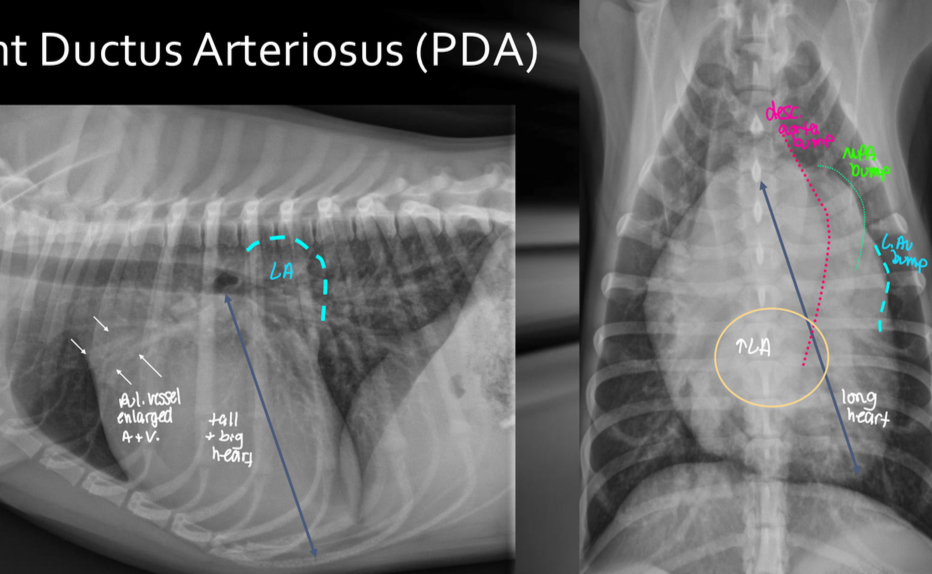

What disease does this dog have

PDA

Roentgen signs of PDA

-BIG LVE, VOLUME OVERLOAD

-triple bump sign on VD (Prox desc. Aorta, MPA, L.Au)

-normal to large pulmonary vessels (hyperperfusion)

±LHF

Pathogenesis of PDA

1.shunt connection between aorta and pul artery

2.high pressure blood from aorta to pul artery —> dilate pul artery

3.hyperperfused lungs

4.dumps blood into left heart

5.big LA and LV

What does the angiocardiography highlight in PDA

-see the shunt

-left ventricular dilation

-opacification of aortic and pulmonary arteries